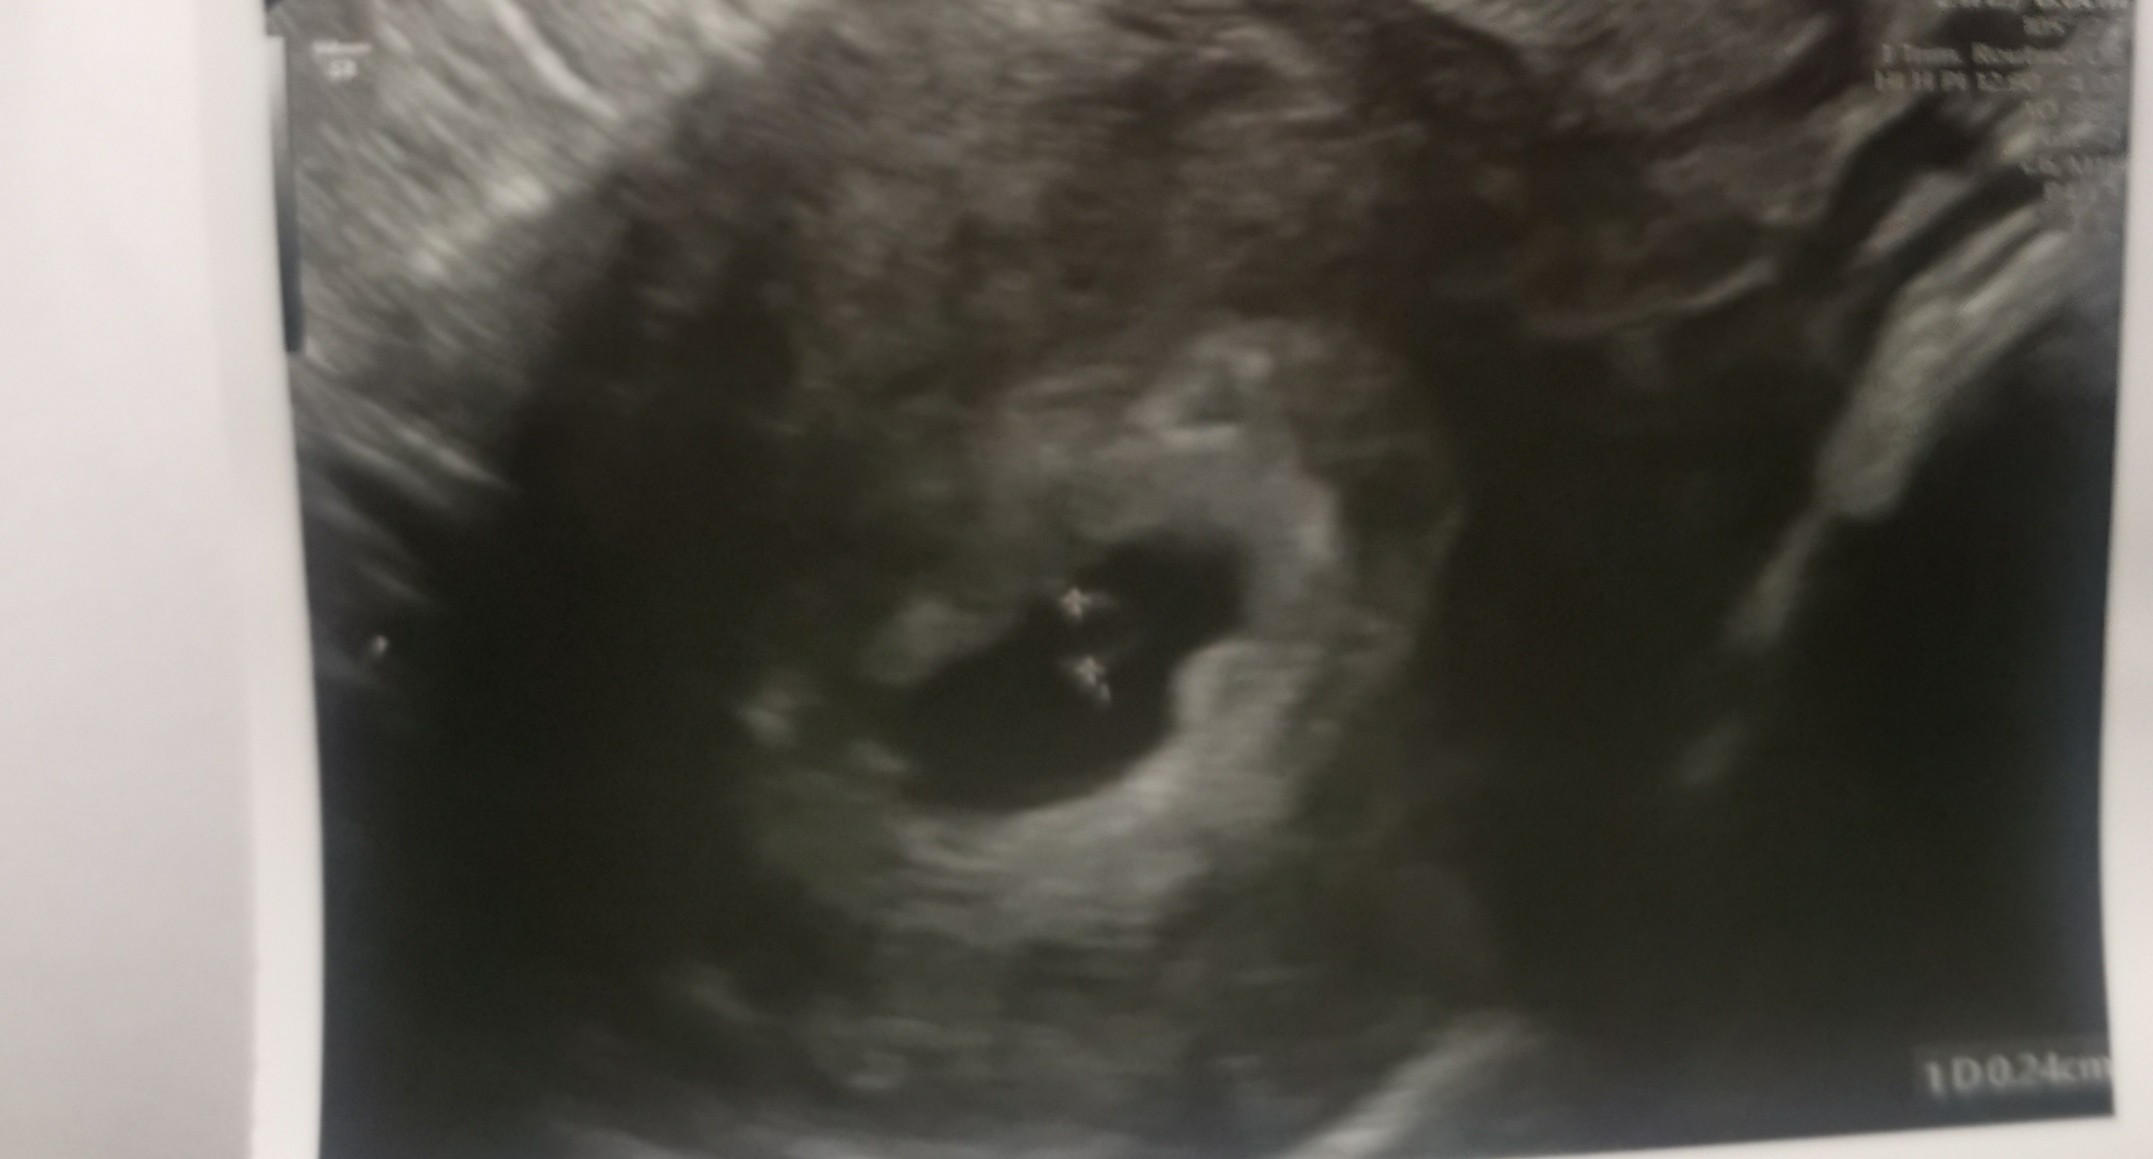

Wszystko jest ok! Ciąża 5+6. W macicy. Nic złego na tym etapie się nie dzieje! Beta ok. Progesteron ok. Ulżyło mi. To było najlepiej wydane 300 zl.![]()